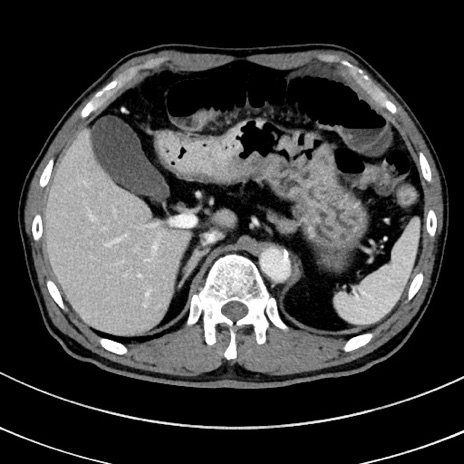

冠状断像

【症例】 60歳代男性

【主訴】 黒色吐物

【現病歴】 4日前から嘔気自覚、2日前の朝食後にも嘔気あり、自分で手で嘔吐反射起こし嘔吐したところ血が混ざっていたため受診。

【既往歴】 5年前汎発性腹膜炎を伴う急性虫垂炎で手術、高血圧、前立腺肥大症、高脂血症

【身体所見】 腹部正中に手術癩痕あり 腹部平坦・軟圧痛なし膨満感あり

【データ】WBC 8400、CRP 4.54